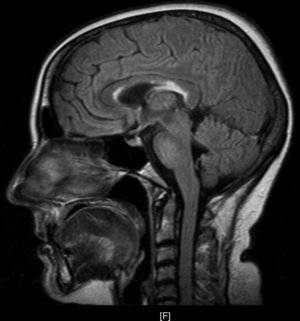

Upon her arrival at the Emergency Department, BP was 154/106 and heart rate was 150bpm. The patient presented convergent strabismus with bilateral miosis, bilateral sixth cranial nerve palsy, and horizontal nystagmus, plus ataxia and abolished patellar reflexes. In the first hours following admission, as the patient was being treated with glucose solution, her level of consciousness decreased and the ataxia and ophthalmoparesis worsened. Complementary testing revealed the following values: K 2.8mmol/L, Ca 11.72mg/dL, GOT 193U/L, GPT 199U/L, PTH 9, TSH<0.05, T4L 2.01; antithyroid peroxidase AB>600; tumour markers and HIV, HVA, HVB, and HVC serology tests all negative. ECG showed supraventricular tachycardia with a rate of 140bpm. Ultrasound revealed a thyroid of borderline size with no nodules. Echocardiography, abdominal ultrasound, gastroscopy, and brain and thoracic-abdominal CTs showed no significant findings. The MRI scan (Fig. 1) revealed deep periventricular alterations, demyelinating lesions in the white matter in predominantly frontal bilateral locations, and well-circumscribed plaques of demyelination in the corpus callosum and pons. All of these signs are compatible with WE.

WE consists of the classic triad of ophthalmoparesis with ataxia and confusional syndrome, although only a third of all patients present the 3 signs simultaneously. Altered mental status presents in 82% of all patients, with manifestations that include disorientation, apathy, lethargy, confusion and agitation, memory impairment, and even stupor and coma. In contrast, ophthalmoparesis presents in 29% of cases and includes horizontal nystagmus, paralysis of the lateral rectus muscles with diplopia and internal strabismus, conjugate gaze palsy, ptosis in rare cases, and miosis in long-standing processes. Ataxia appears in 23% of cases with unstable tandem gait, short strides, and increased base of support. Other signs may include polyneuropathy as a manifestation of nutritional deficiency, and tachycardia with postural hypotension due to autonomous nervous system disorders or cardiac beriberi. Diagnosis is basically clinical, and the disease is reversible with administration of thiamine. MR imaging studies provide additional information with a low sensitivity of about 53% and a higher specificity of 93%. Studies show increased T2-weighted signal intensity in the periventricular area, mamillary bodies, and periaqueductal grey matter, as well as demyelinating lesions in the cortex and corpus callosum.3